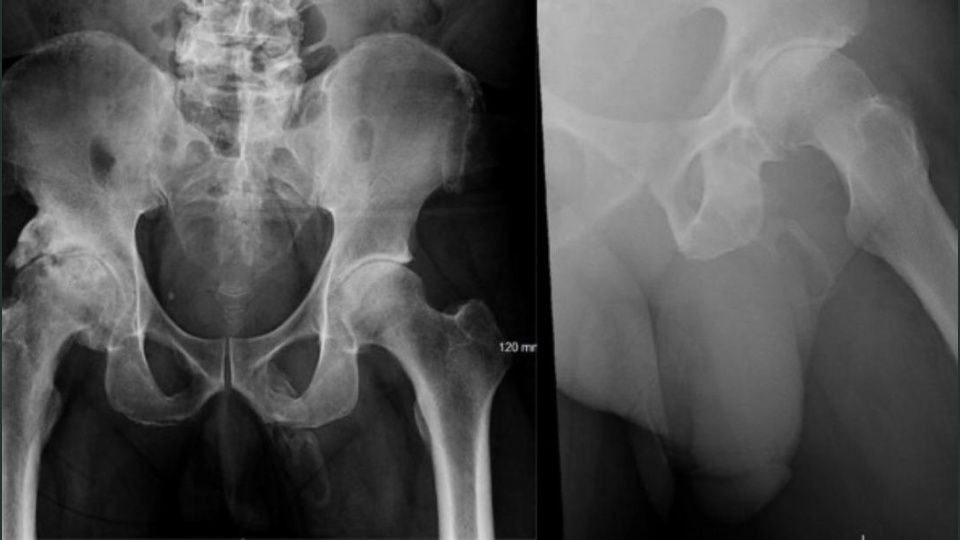

Al realizarle una radiografía para verificar que no se había roto la cadera mostró tejido óseo formándose en su pene.

Mientras lo revisaban, los médicos le tomaron una radiografía de la pelvis para verificar que no había huesos rotos, pero encontraron algo más extraño de lo que esperaban.

Lo diagnosticaron con una osificación, lo que significa que una parte del cuerpo se convierte lentamente en hueso.